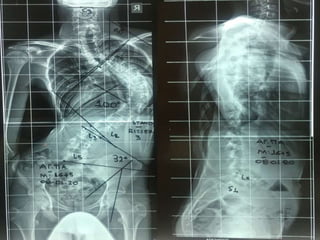

Θ5 – Ο2 (Α) 40ο

King IV

 Α. Παρ.

Θ – 15+3